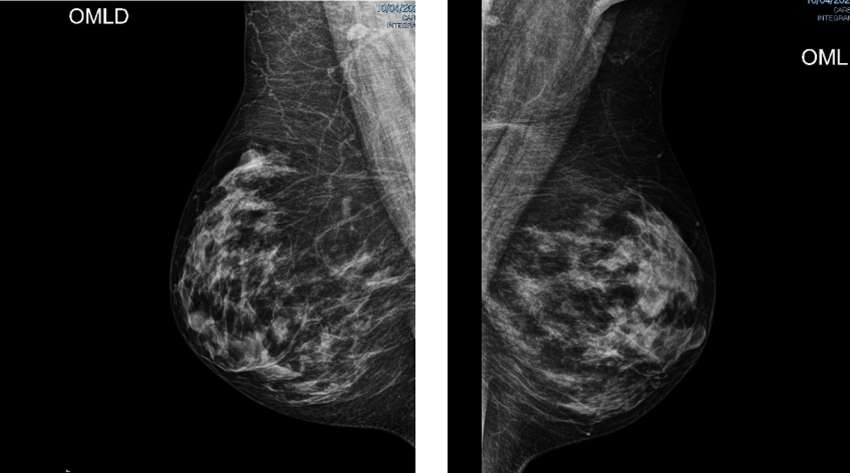

Imágenes Mx

Informe MX:

Hallazgos:

Piel y tejido subcutáneo sin alteraciones.

La unidad areola y pezón normal.

Mamas densas, con distribución heterogénea, observado algunos contornos nodulares, isodensos parciales, bilaterales más evidentes a derecha.

No se reconocen microcalcificaciones agrupadas de manera sospechosa.

Conclusión:

Mamas densas con probable nódulos bilaterales

Se complementará con ultrasonido

Birads 2

ACR C